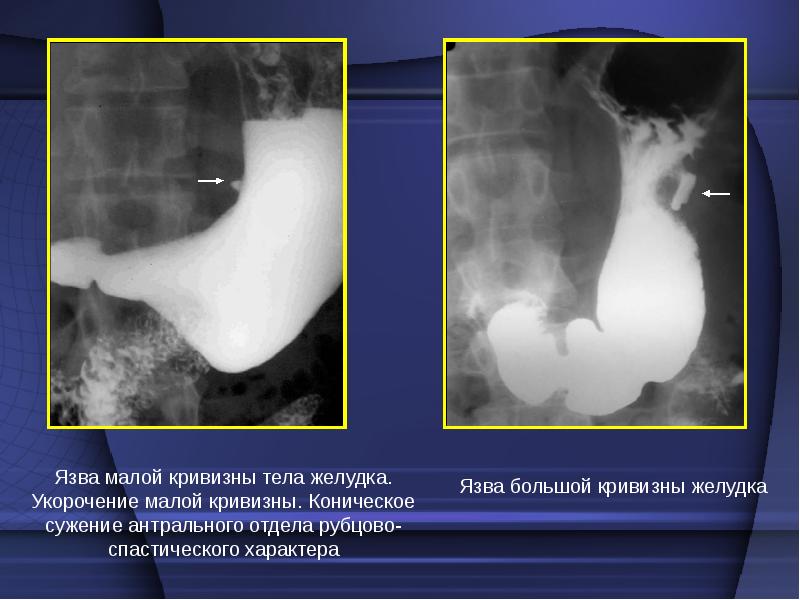

Рентгенологическими признаками язвенного процесса в желудке являются

Рентгенологическими признаками язвенного процесса в желудке являются 115 фото